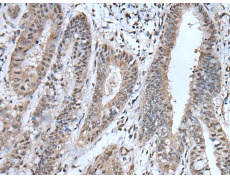

IHC positive control: |

Human liver cancer and human breast cancer |